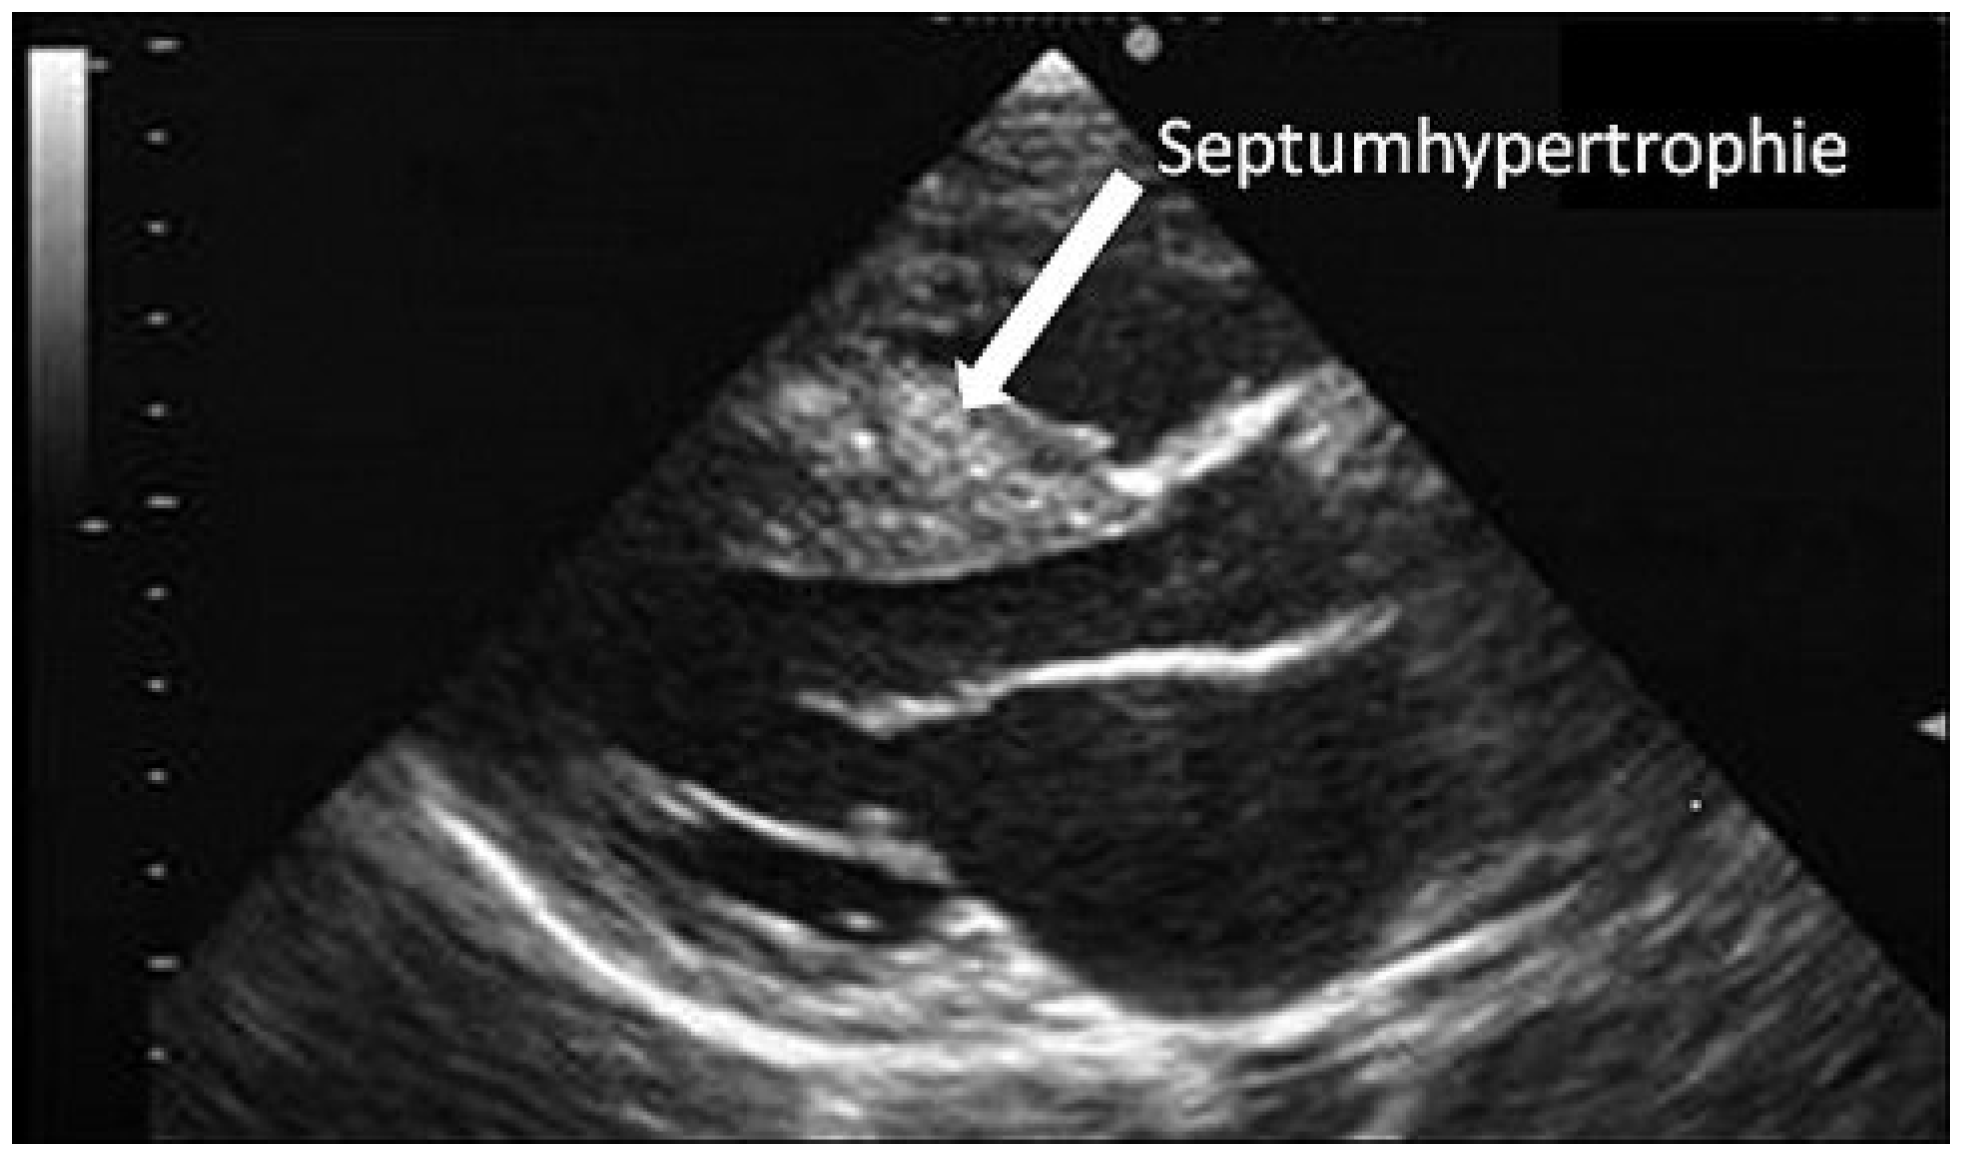

In mehreren Fallstudien wird einerseits eine Hypertrophie des Myokards, insbesondere des Septums (Abbildung 2), beschrieben, wobei diese Veränderungen zum Teil auch auf den Trainingseffekt von Kraftsport (AAS-Missbrauch vor allem bei Bodybuildern) zurückzuführen sein dürften [1,4,5]. Des Weiteren werden eine Ventrikeldilatation sowie Beeinträchtigungen der systolischen und diastolischen Funktion beschrieben [6]. Generell ist die LVH als ein Prädiktor für erhöhte kardiovaskuläre Morbidität und Mortalität zu betrachten [7]. Welche Bedeutung diese spezifischen Veränderungen jedoch auf die individuelle Prognose eines Patienten haben, bleibt unklar, wenn diese Veränderungen auch im Allgemeinen mit einer Aggravierung des klinischen Zustandsbildes einhergehen.

Abbildung 2. Echokardiographie. Konzentrische Hypertrophie des linken Ventrikels eines 37-jährigen Bodybuilders mit AAS-Missbrauch.